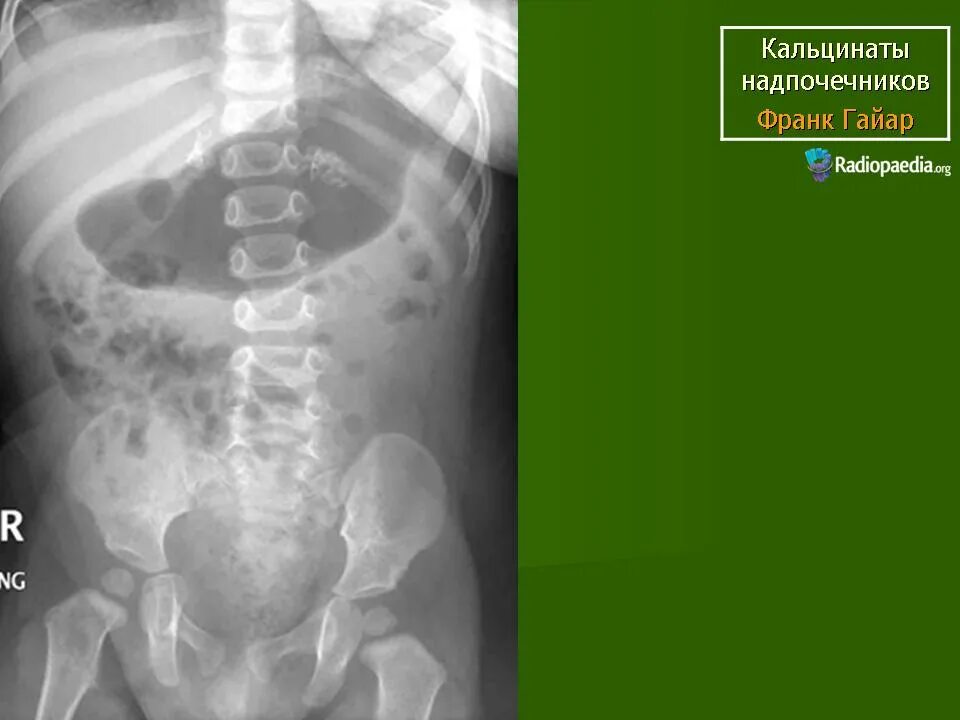

Обызвествление в проекции